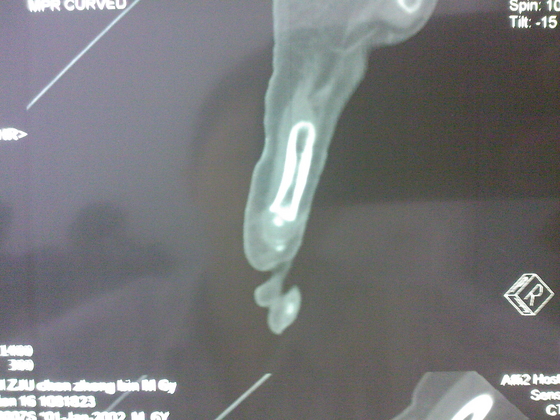

把病理送浙一医会诊后诊断为:骨外软骨瘤。同时做了CT检查。暂未予治疗。

今天把创面情况跟CT发上请大家看看。

继续发CT片

继续还有几张。